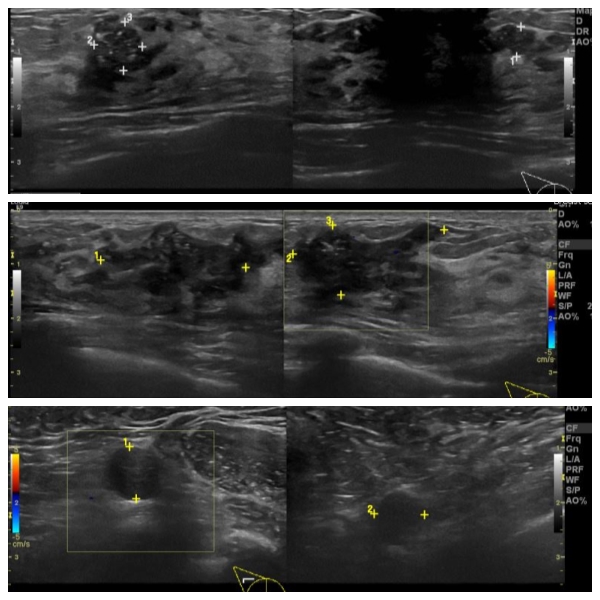

우측 겨드랑이 멍우리로 내원하신 40대 여성분으로 우측 유방의 7시 방향서 3cm 떨어진 거리에 만져지는 혹과, 7시 방향 유륜 밑 중앙핵 생검 시행하여 7시 유두 밑 유관암, 7시 3cm 거리 혹은  침윤성 암 진단 되었고, 우측 겨드랑이 만져지는 멍우리 세포검사 시행하여 전이암으로 진단 되었습니다.